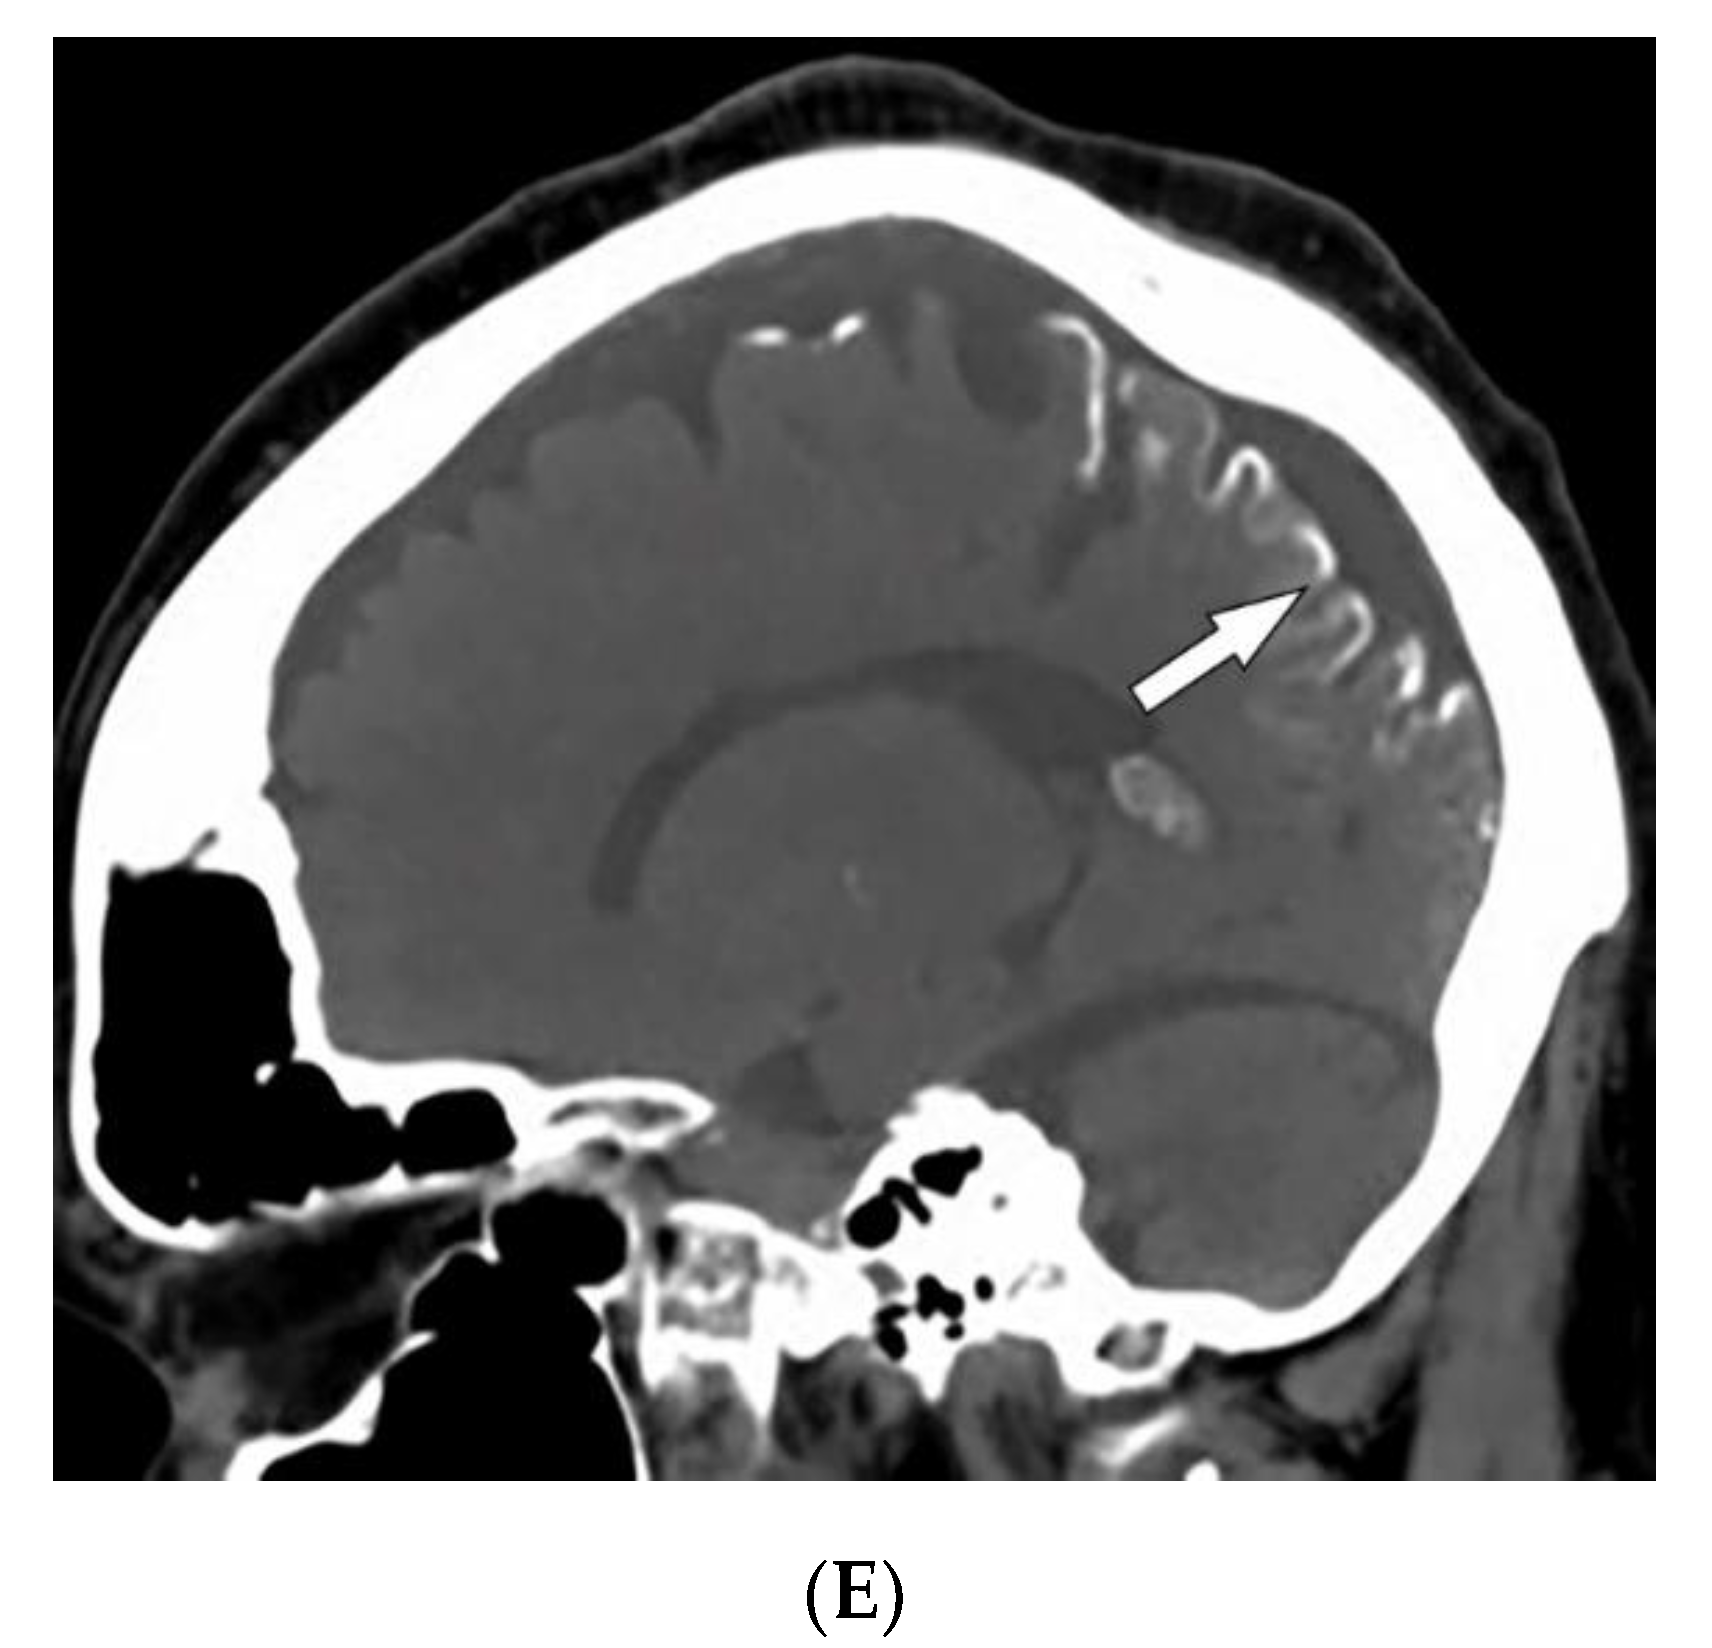

3.3. Sturge–Weber Syndrome

| Sturge–Weber syndrome | Port-wine stains Leptomeningeal capillary malformation Glaucoma | Parieto-occipital cortical hemiatrophy Tram-track calcification Calvarial thickening |